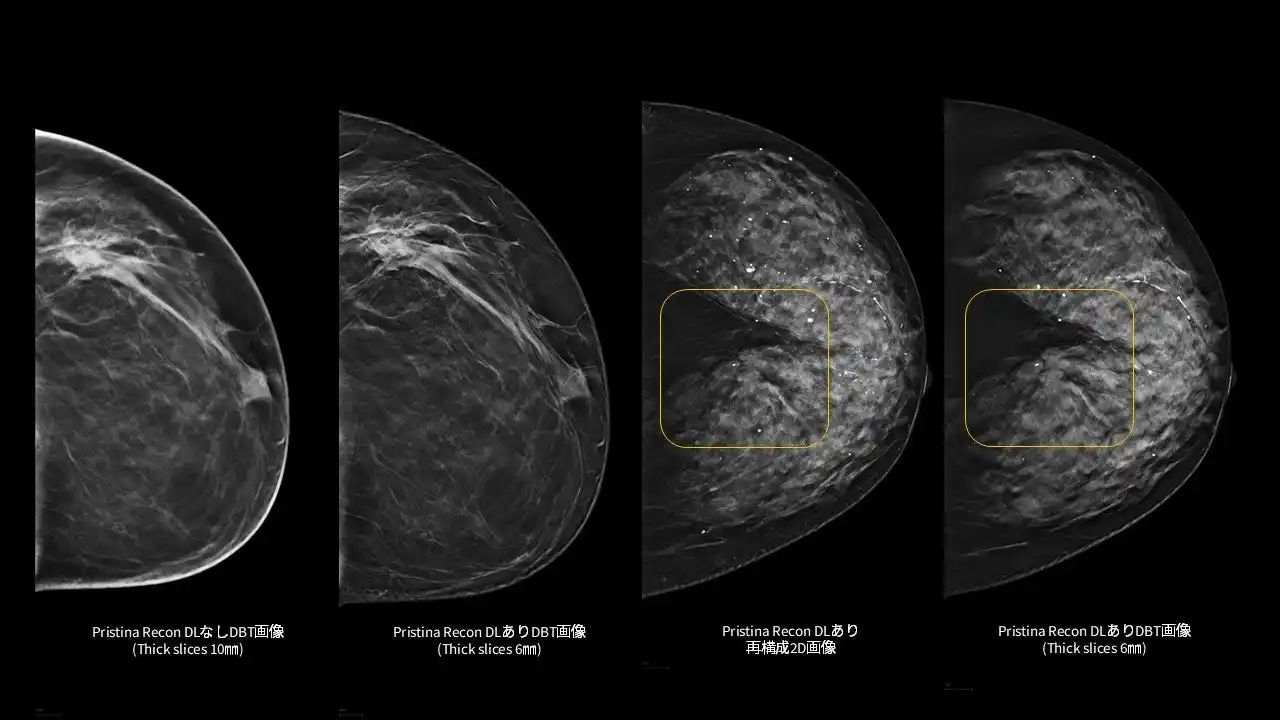

「Pristina Recon DL」¹は、MRIの画像再構成にディープラーニングを適用したGEヘルスケア独自のAIR(TM) Recon DL技術を基盤としています。本アプリケーションで、乳房のデジタルブレストトモシンセシス (DBT/3Dマンモグラフィ) 技術の更なる可能性を追求し、低線量での撮影でも、より高画質な画像の提供を目指します。また、アーチファクト(虚像)や視覚的ノイズの低減を図り、微細構造の視認性の向上にも寄与します。²,³ |

「Pristina Recon DL」は、ディープラーニングと逐次近似再構成技術を活用した、デジタルブレストトモシンセシス(DBT/3Dマンモグラフィ)向けの画像再構成技術です。また、被ばく線量を増加させることなく、高画質で安定したDBT/3Dマンモグラフィ画像の提供を目指します。 |

さらに、ディープラーニングを用いた高度な画像再構成技術により、アーチファクト(虚像)や視覚的ノイズを低減し、微細構造の視認性を向上させます。これにより、DBT/3Dマンモグラフィおよび再構成2D画像の双方において、読影に必要な情報をより明確に可視化し、診断を支援する読影環境の向上に貢献します。 |